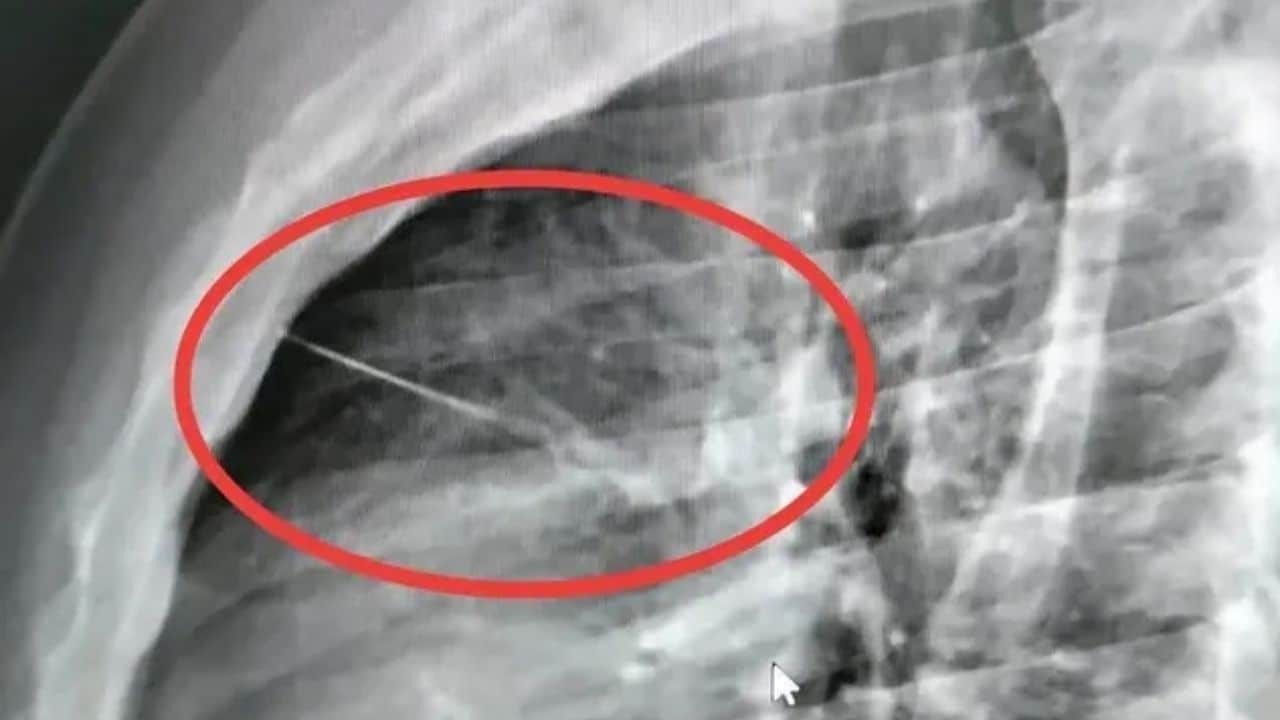

Vật thể lạ sau đó được xác định là một cây kim dài khoảng 7 cm. Ảnh: SiamRath

Tại bệnh viện, các bác sĩ tiến hành chụp X-quang để xác định nguyên nhân cơn đau. Kết quả khiến đội ngũ y tế bất ngờ khi phát hiện một vật thể nhỏ, sắc nhọn nằm bên trong lồng ngực bệnh nhân. Vật thể này sau đó được xác định là một cây kim dài khoảng 7 cm. Vị trí của cây kim nằm gần tim, gây nguy cơ cao đối với tính mạng của bệnh nhân.